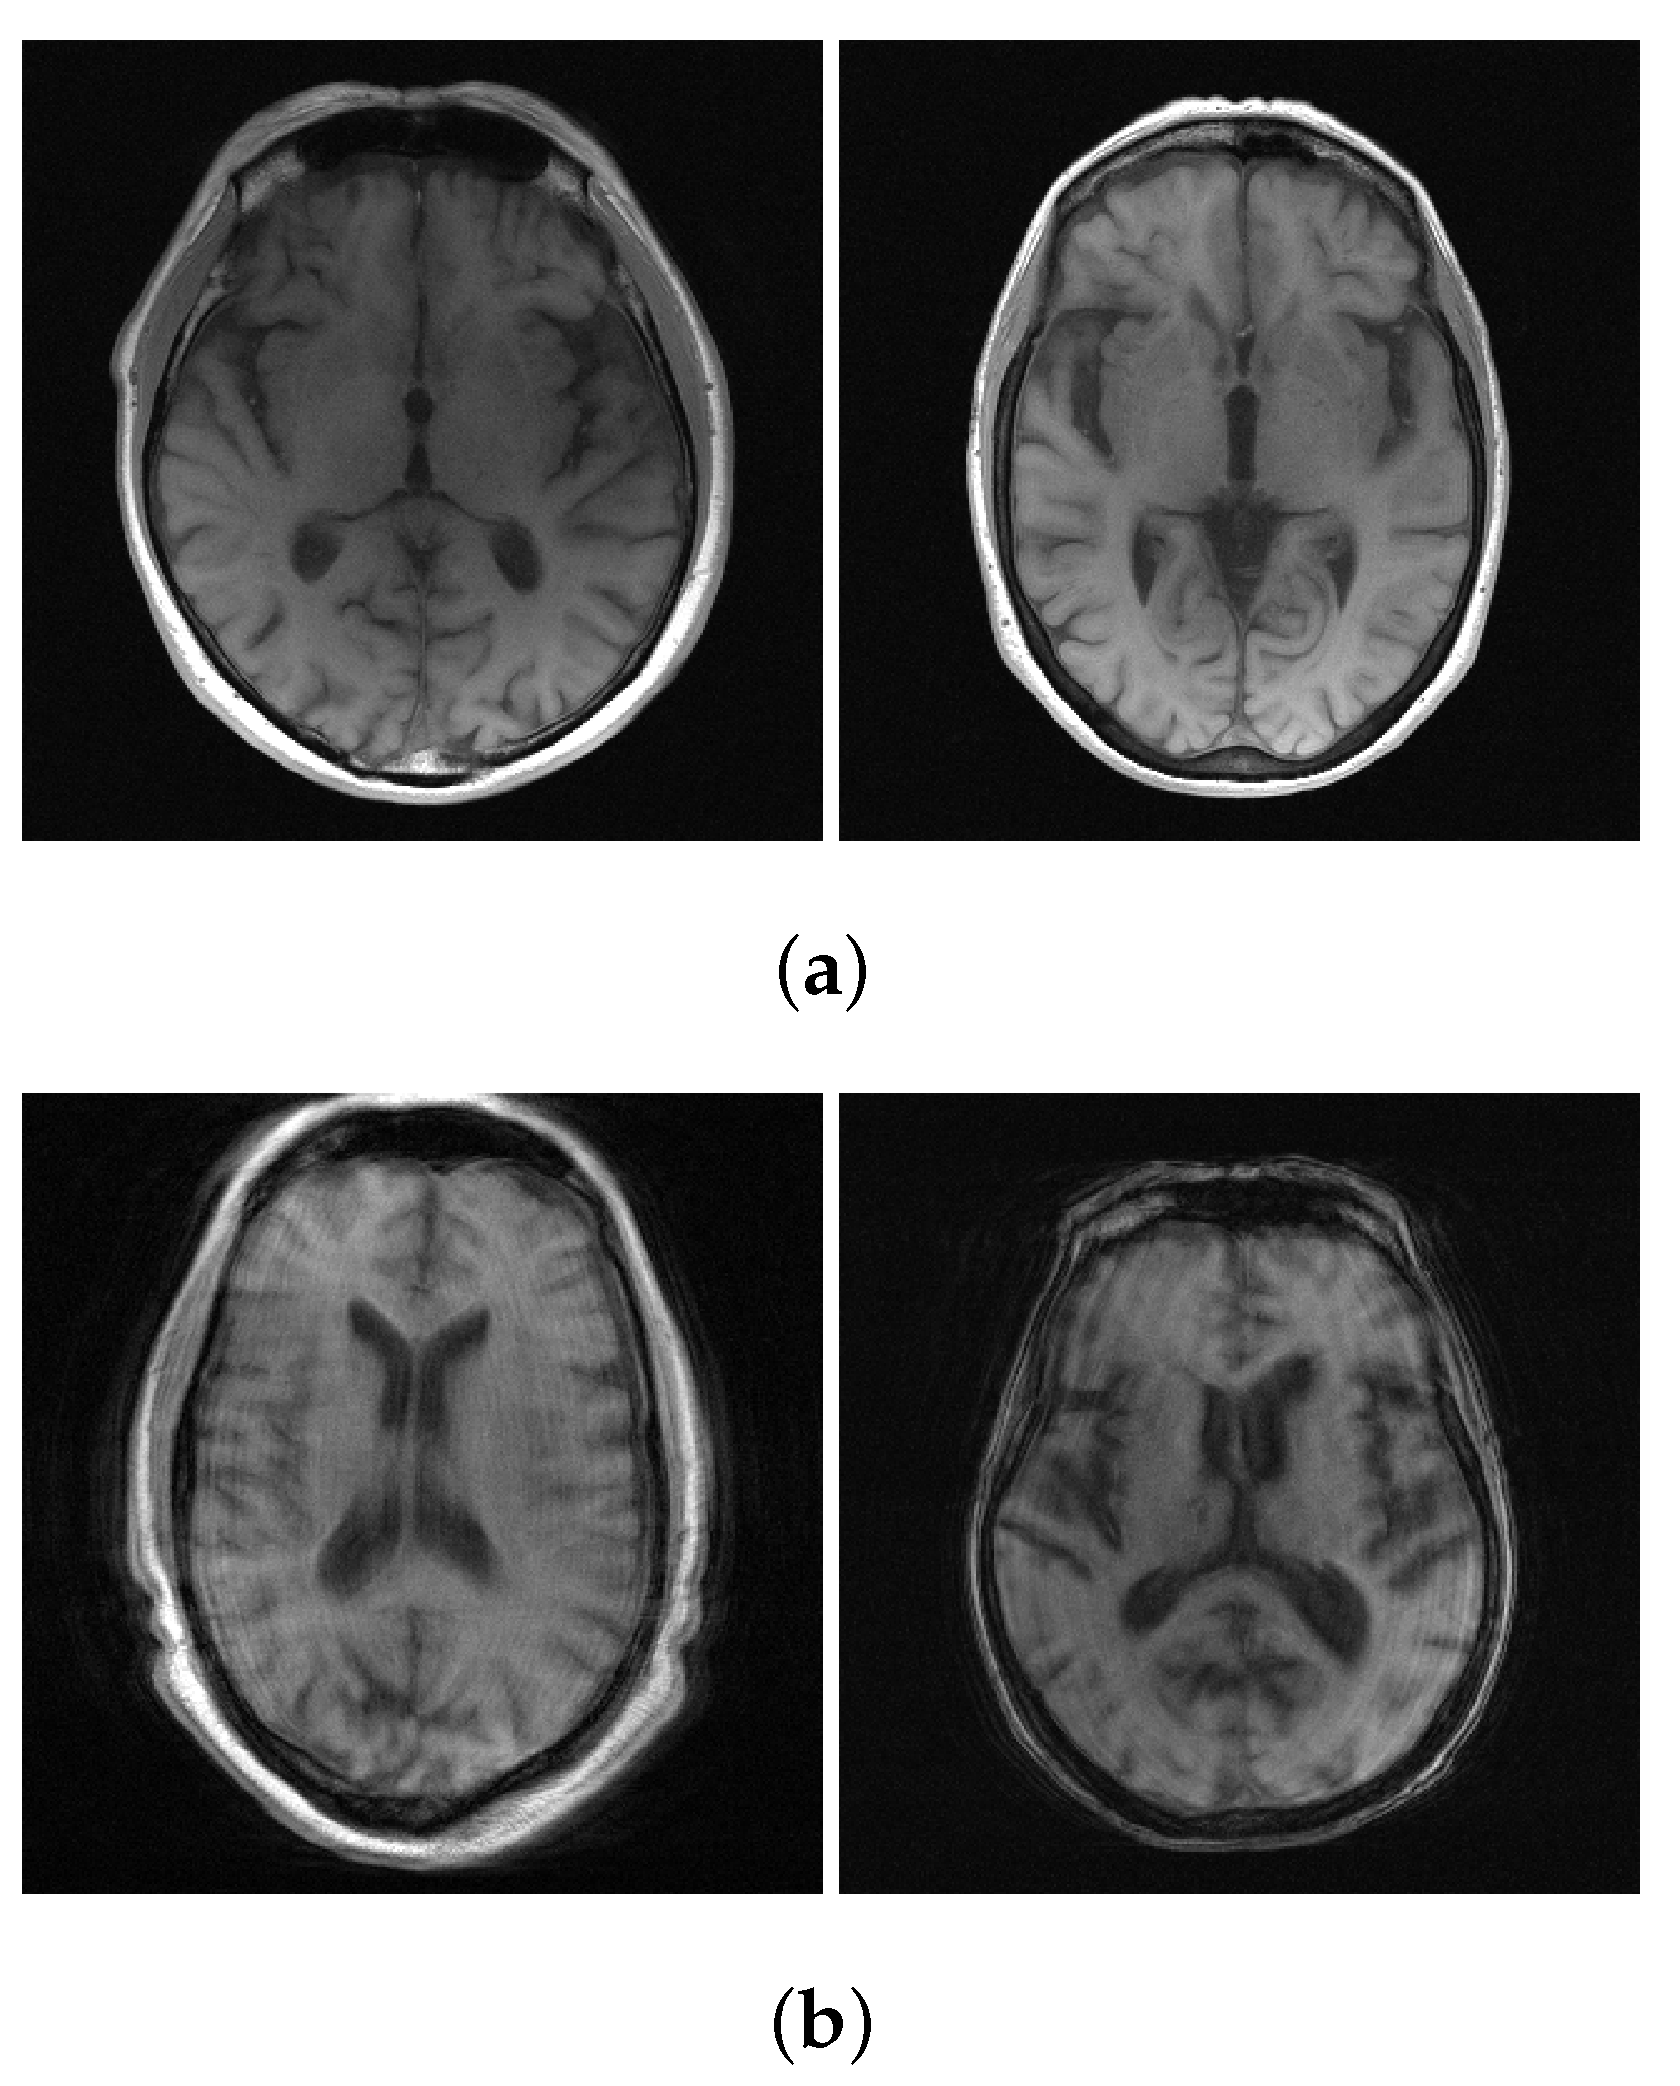

4.2. Results